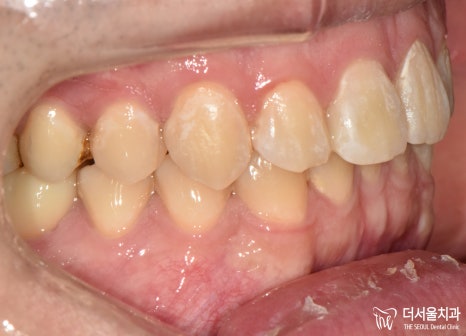

측면으로 봤을 때도

좀 더 치열이 가지런해진 것과,

각자 제 위치를 찾아가는 것이

눈에 띄었습니다.